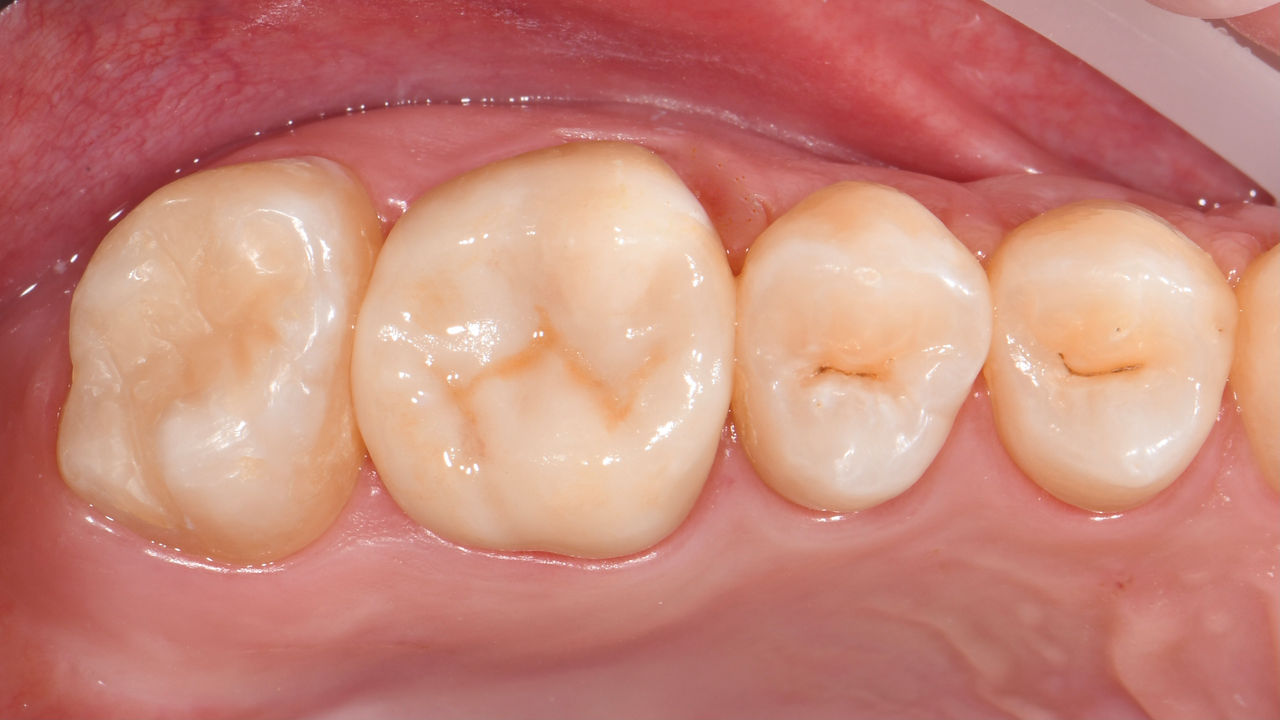

Primer molar superior en 75 minutos

Corona individual IPS.emax CAD

Un escaneo rápido y muy preciso, un software de diseño manejable e intuitivo, combinado con una unidad de fresado y tallado que completa una restauración en pocos minutos, suponen un aumento significativo de la eficiencia y una mayor satisfacción de los pacientes con mi clínica.

Antes: El diente 26 presenta caries y una restauración de composite directa defectuosa.

Después: Corona de cerámica de disilicato de litio altamente estética y funcional.